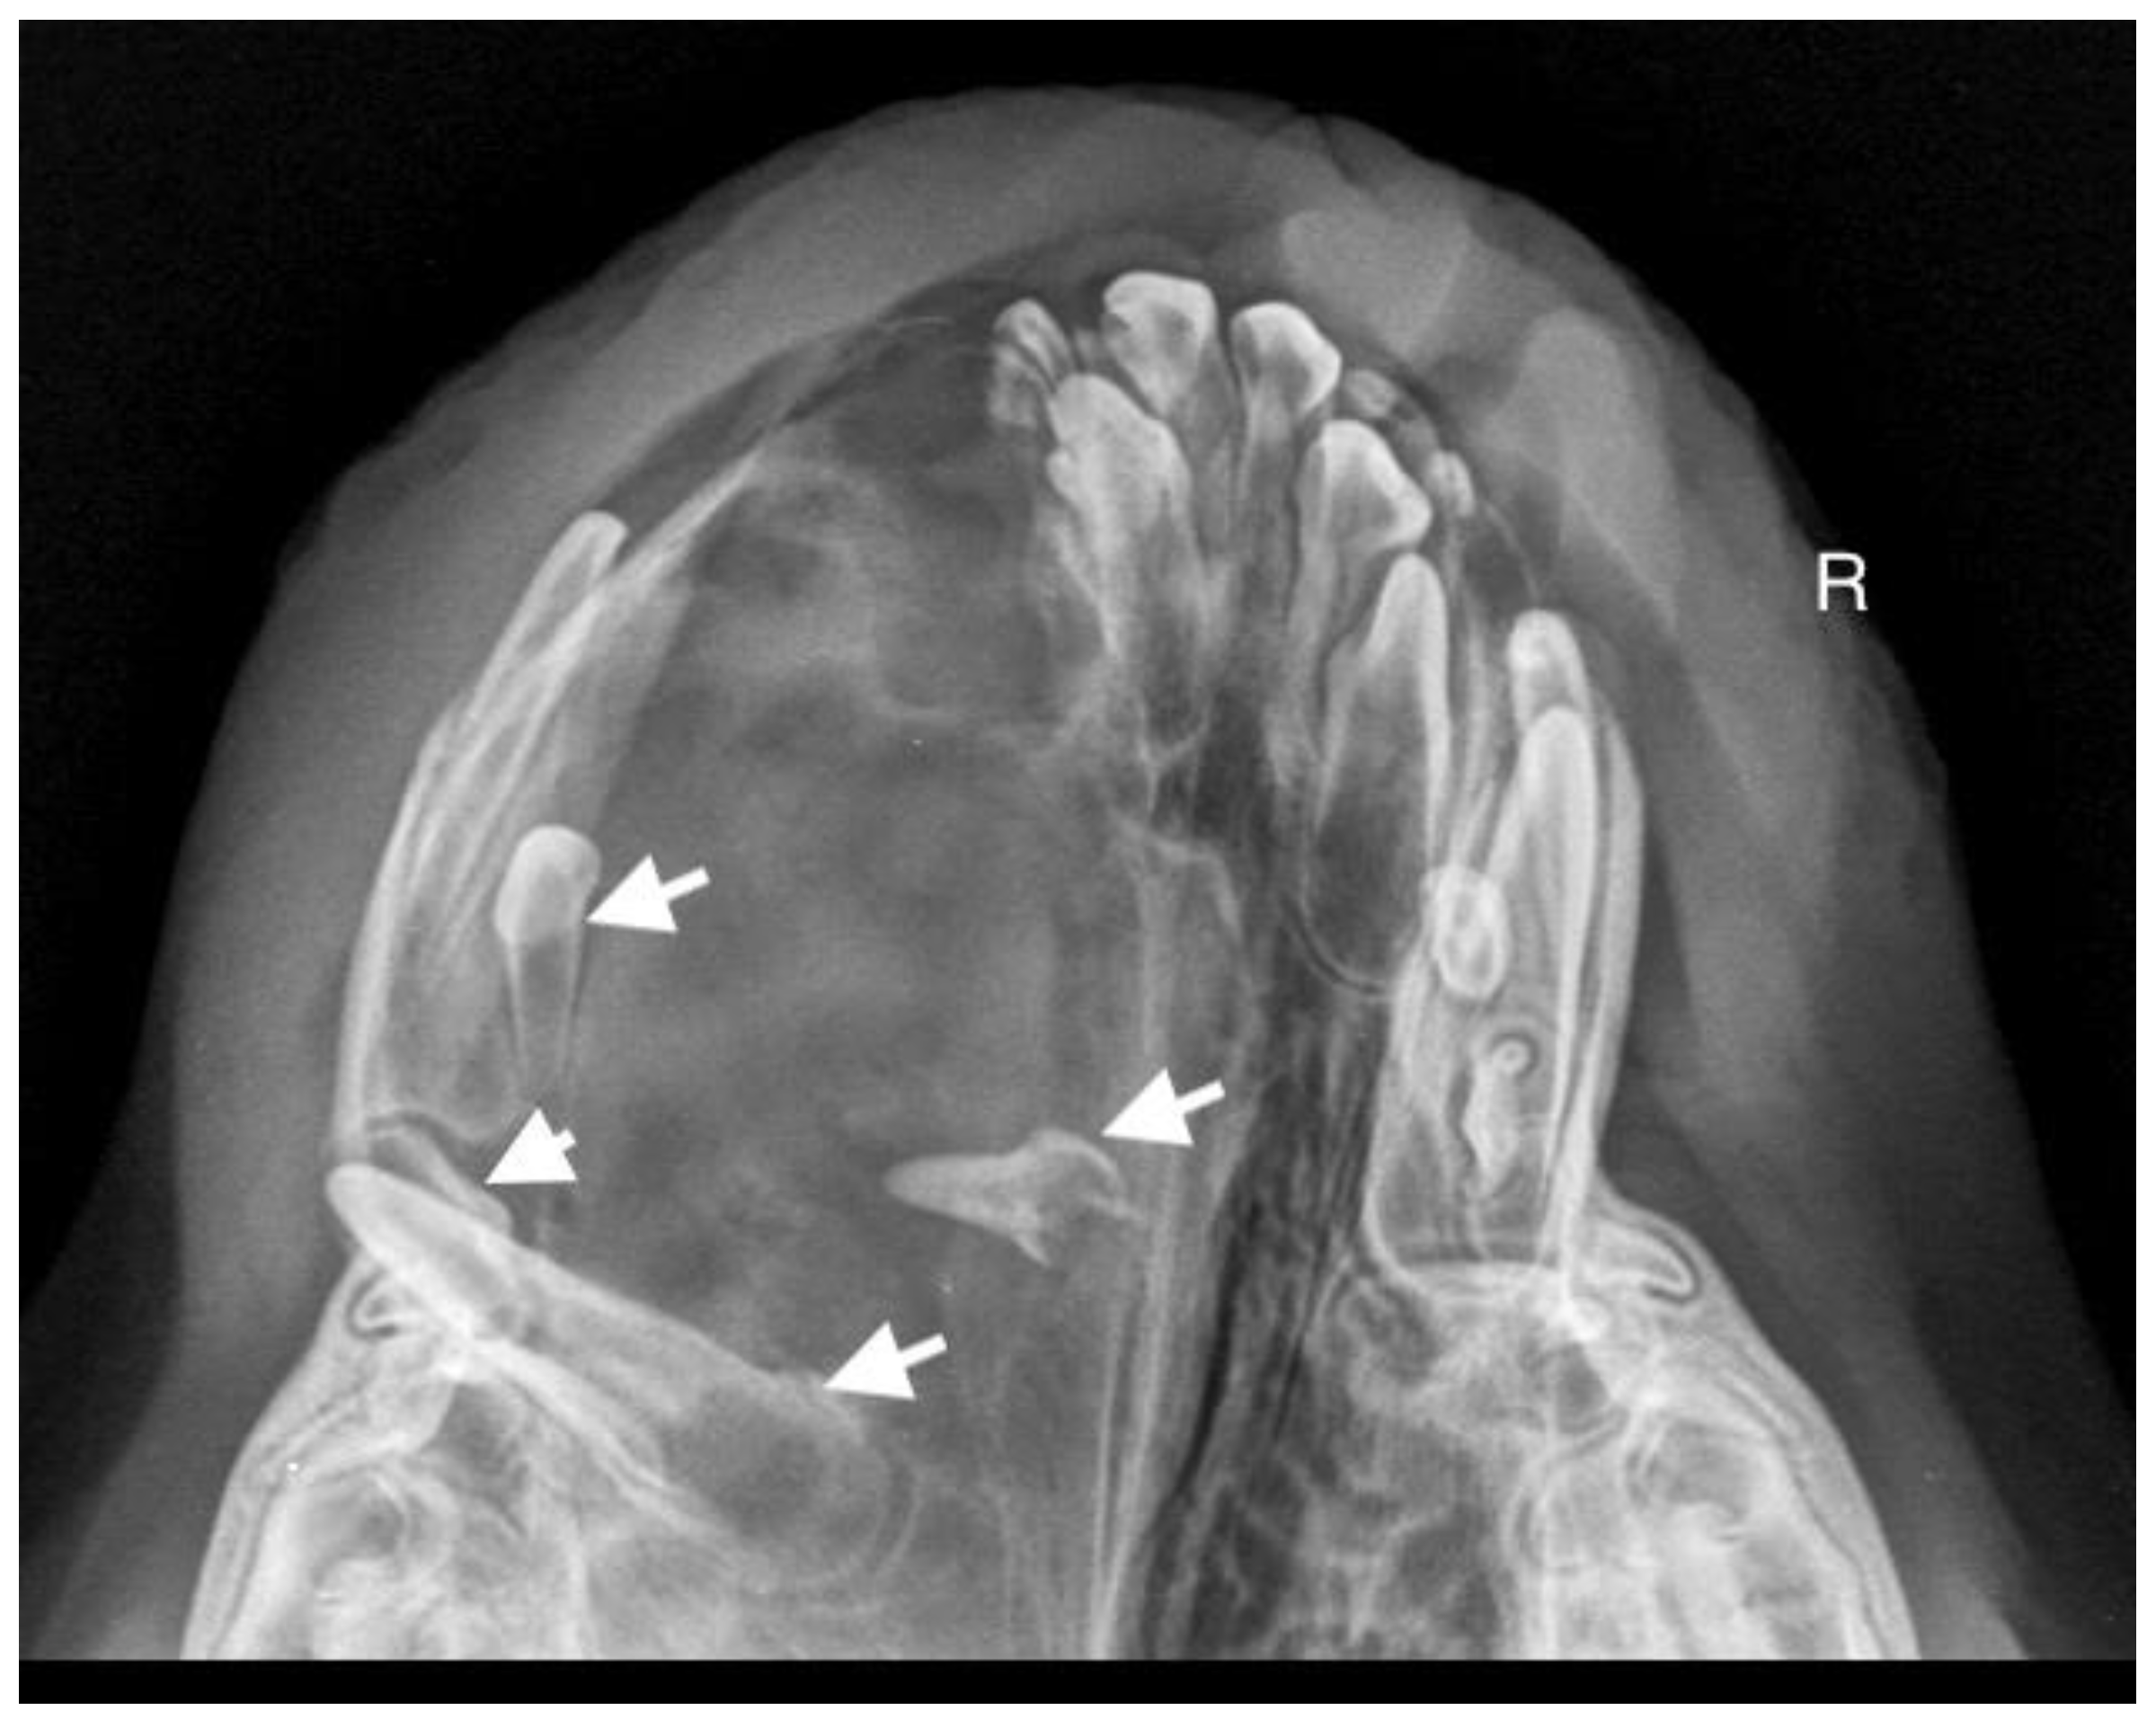

A 7-month-old male Rottweiler was referred for consultation because of severe swelling on the left side of the jaw, with a suspected jaw tumor. Clinical examination revealed no abnormalities in the aforementioned lymph glands and no soreness on palpation. Intraoral examination on the left side revealed severe asymmetry, with enlargement of the facial soft and hard tissues, an absence of permanent teeth, and buccal displacement of deciduous teeth. On the left side, rhinoscopic examination revealed normal anterior nostrils and a left nasal aperture with a lack of patency from the level of the nasal bony inlet to the posterior nostrils. A roentgenogram in the dorsal–ventral projection showed the presence of four ectopic teeth in the maxilla, with the formation of a dentigerous cyst (Figure 2). Using the CLP technique, the ectopic teeth were removed and the cyst walls were lanced. The bone loss caused by the cyst was 7.3 cm × 4.6 cm, and the jawbone left behind was too thin to provide a scaffold for the surrounding tissues and to ensure nasal cavity patency. From a 5 cm pellet of hydroxyapatite polymer material with curdlan previously soaked in saline (according to the manufacturer’s instructions), longitudinal flaps of 5 cm long, 1 cm wide, and 0.1–0.2 cm thick were cut and placed in the bony defect to strengthen the bony scaffolding of the jaw and nasal septum (Figure 3). The gingival flap was sutured with a single suture using 4-0 monofilament material. The first radiological follow-up was performed after 4 weeks, but due to the size of the defect and the size of the pellets of material used, the hydroxyapatite obscured the structures in the nasal cavity, preventing accurate assessment. A rhinoscopic examination revealed patency of the left nasal cavity. It was decided to conduct a radiological follow-up 6 months after the procedure, but the owner, for personal reasons, did not attend the follow-up appointment. After 12 months, another roentgenogram was performed, where a properly healed jawbone with closure of the cyst cavity could be observed. The nasal septum was formed properly, and the resulting bony scaffolding resulted in patency of the left nasal aperture, along with normal airflow on the left side (Figure 4).

Figure 2. X-ray in dorsal–ventral projection before surgery. On the left side, four ectopic teeth (marked with arrows) with the formation of a dentigerous cyst are visible.